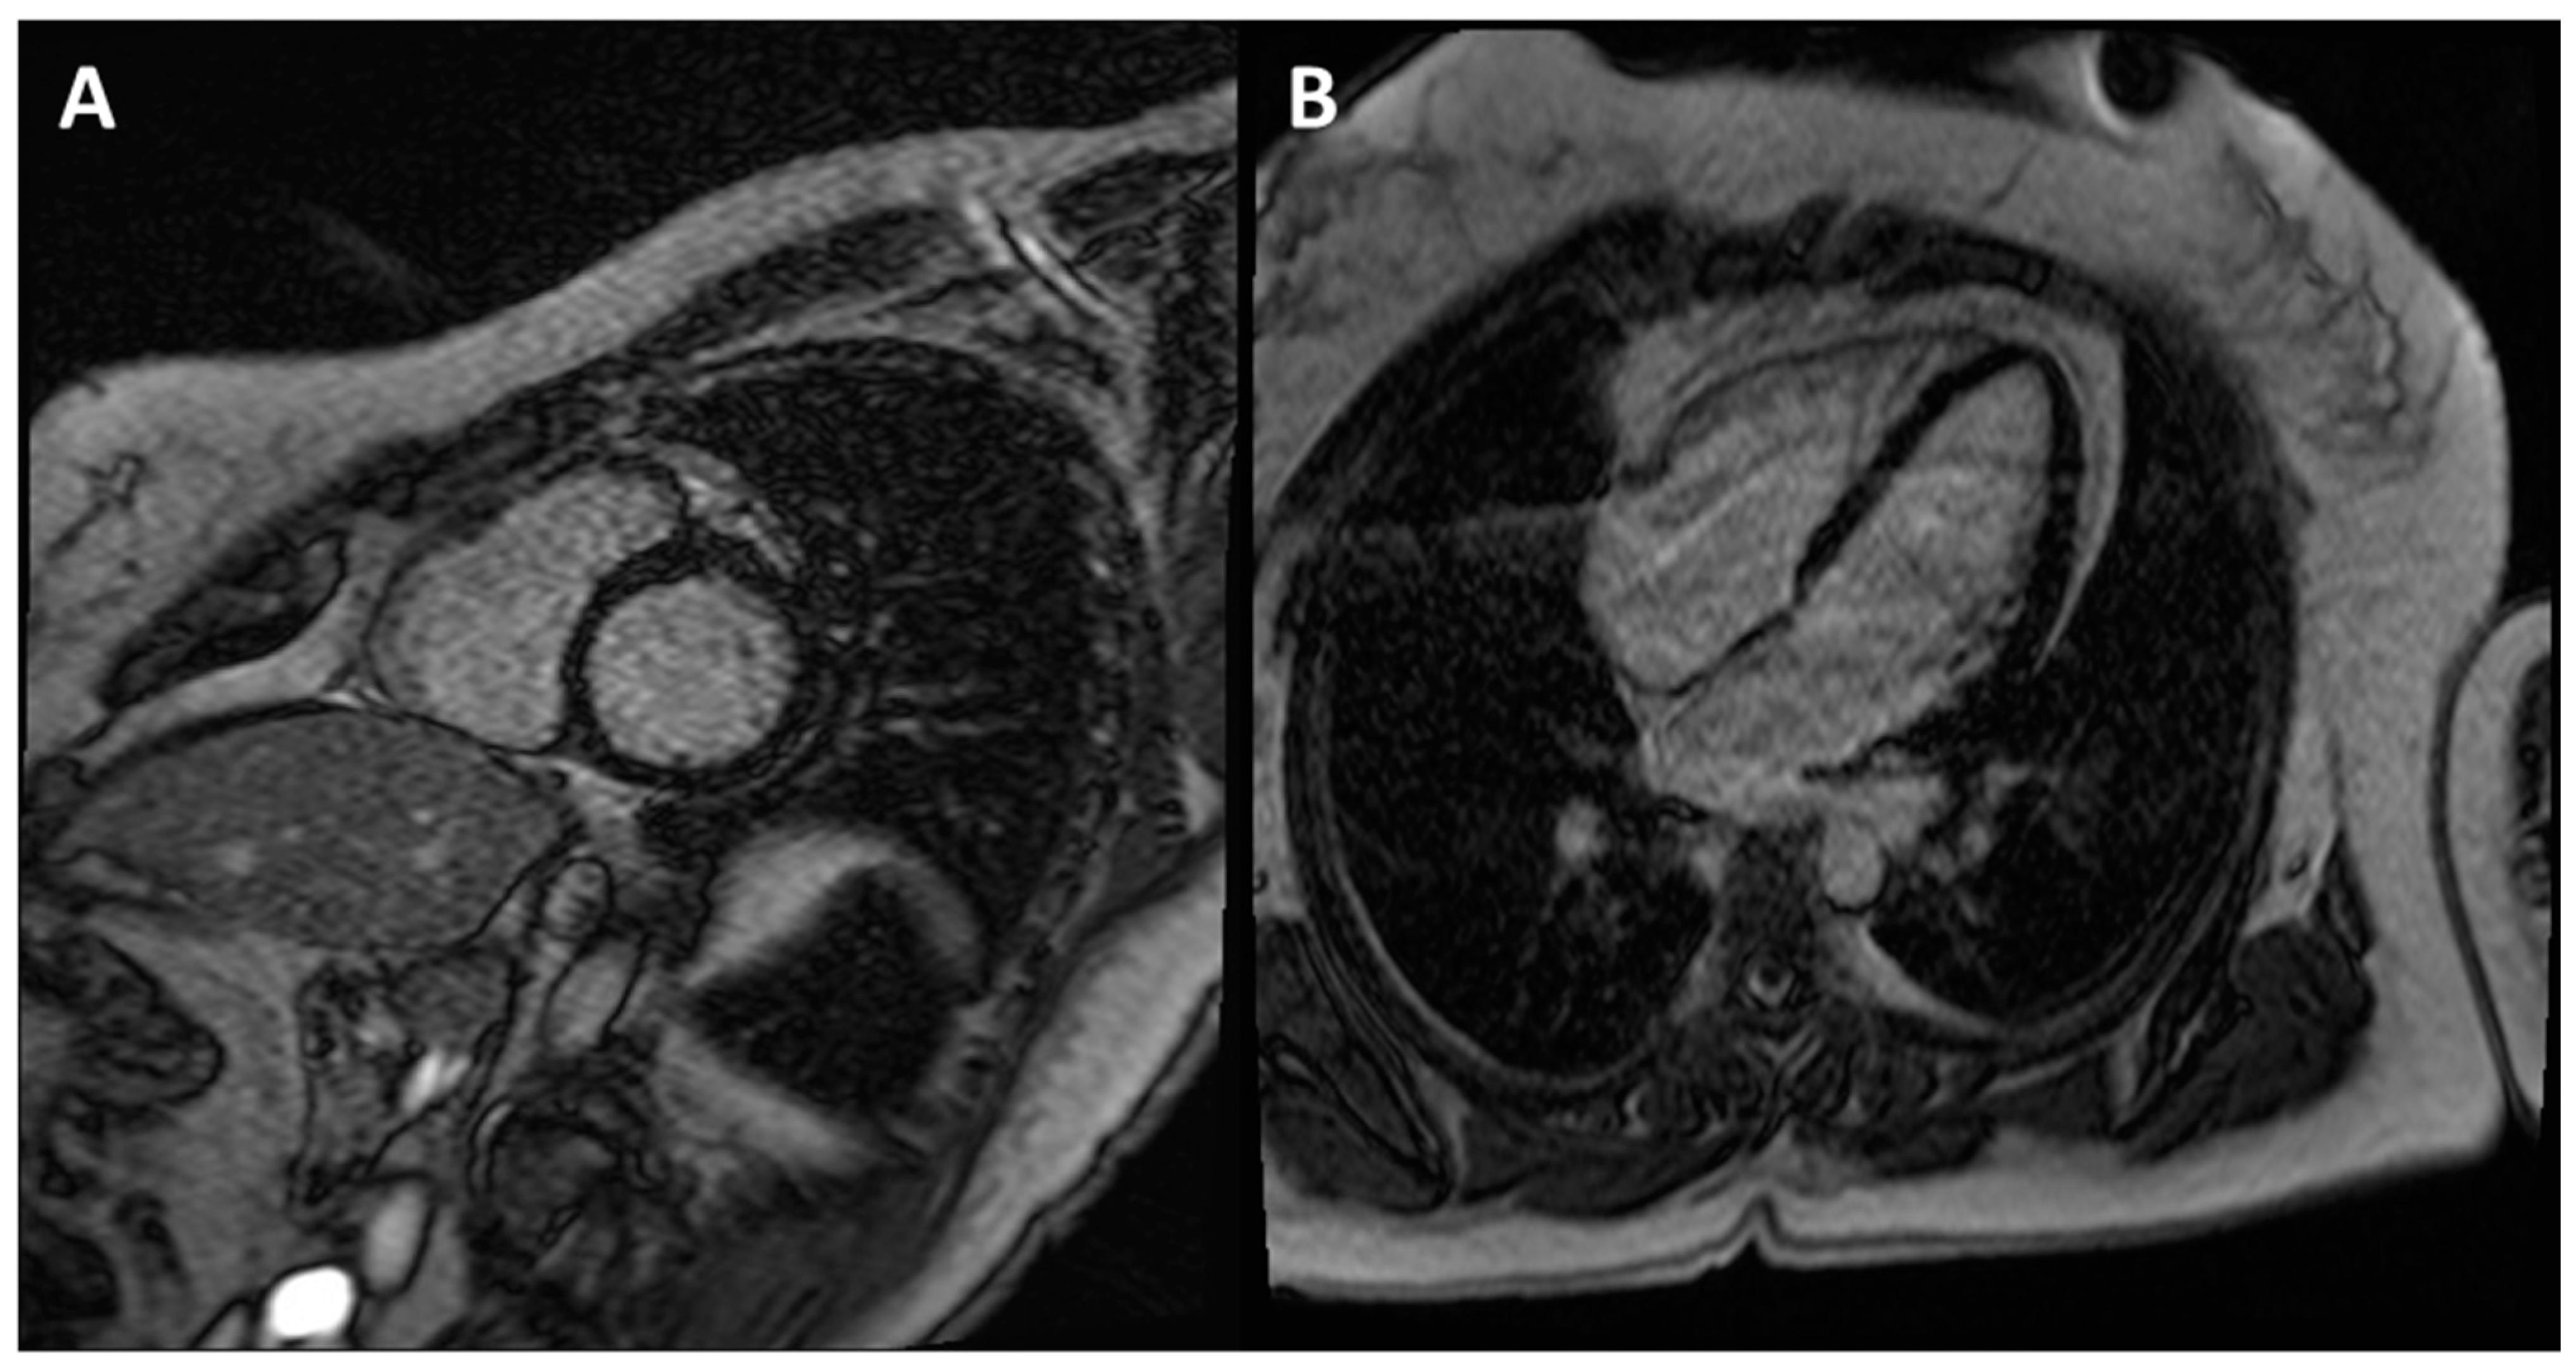

2.4.1. Hypertrophic Cardiomyopathy

2.4.2. Arrhythmogenic Cardiomyopathy

3. The World of ACM and DCM: How “Complex Imaging” (Electroanatomic Mapping) Directs Diagnosis and Invasive Management

3.1. Arrhythmogenic Cardiomyopathy

3.2. Dilated Cardiomyopathy